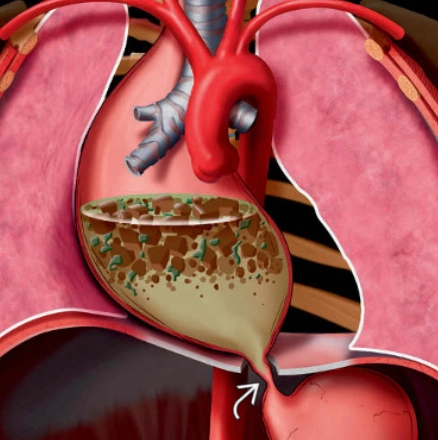

U mạch bạch huyết trung thất (Mediastinal Lymphangioma)